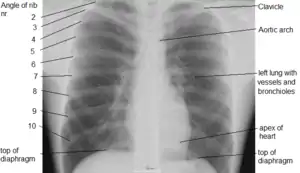

X-ray image of the chest showing the internal anatomy of the rib cage, lungs and heart as well as the inferior thoracic border–made up of the diaphragm.

An X-ray of a human chest area, with some structures labeled

The contents of the thorax include the heart and lungs (and the thymus gland); the (major and minor pectoral muscles, trapezius muscles, and neck muscle); and internal structures such as the diaphragm, the esophagus, the trachea, and a part of the sternum known as the xiphoid process). Arteries and veins are also contained – (aorta, superior vena cava, inferior vena cava and the pulmonary artery); bones (the shoulder socket containing the upper part of the humerus, the scapula, sternum, thoracic portion of the spine, collarbone, and the rib cage and floating ribs).